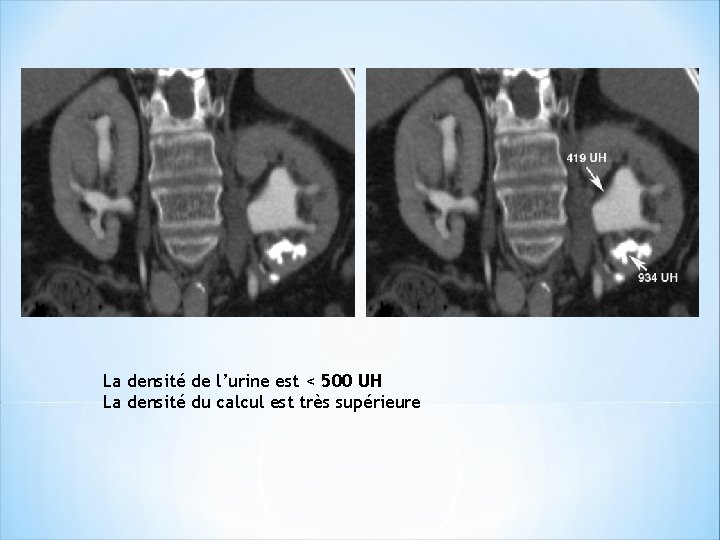

Intérêt de la dilution de l’urine: Urine non diluée a densité >>> celle de la plupart des calculs. >>> La plupart des calculs sont masqués. >>>>phase sans injection++ *Améliorer la visibilité des calculs sur la phase excrétoire: >>>>diluer les urines et distendre les cavités : ( densité< 500 UH). - absorption d’un litre d’eau – perfusion de 250 ml de sérum φ – furosémide : 10 mg IV

La densité de l’urine est < 500 UH La densité du calcul est très supérieure